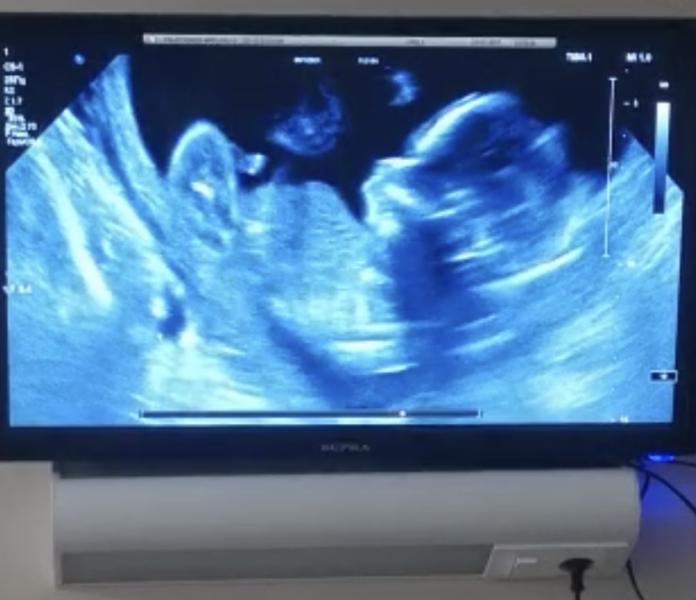

Прошла 2 скрининг, очень переживала, но зря. Все хорошо, подтвердили сыночка,махал ручкой маме и папе, срок на момент скрининга был 20.5, 366 грамм счастья❤️❤️❤️

Поздравляю!) на фото будто личико ещё одно из темноты выглядывает )